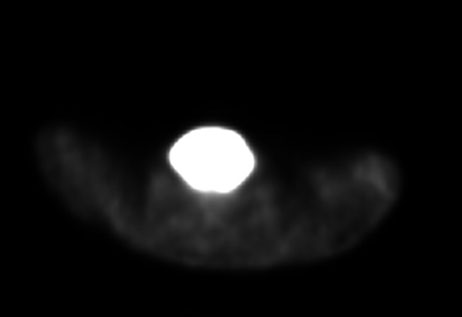

A whole-body PET-CT done revealed an intensely fluorodeoxyglucose (FDG) avid enlarged thyroid gland, reaching posteriorly to the prevertebral spaces and inferiorly to the retrosternal and upper paratracheal space without the presence of suspicious lymph nodes (Figure 7).

Figure 7: Axial PET-CT image (2025) showing an intensely FDG avid enlarged thyroid gland, reaching posteriorly to the prevertebral spaces.

Share Image: